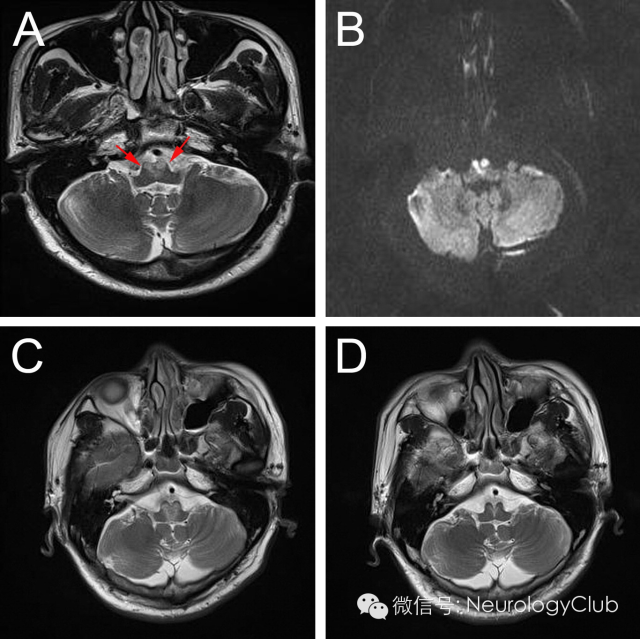

延髓内侧由椎动脉和脊髓前动脉分支供血,其中延髓内侧上1/3由椎动脉旁分支供应,下2/3由双侧脊髓前动脉及其汇合而成的前正中动脉延髓支供应。双侧延髓内侧梗死血管病理学改变以大动脉粥样硬化最为常见,其次是小穿支动脉病变,另外也有栓塞、动脉夹层、动脉炎或合并先天血管变异等病因报道。影像学特点头颅MRI检查,尤其是DWI对双侧延髓内侧梗死的早期诊断有很大的帮助。其影像学表现为磁共振显示双侧延髓内侧类似“心型”或“Y形”的长T1长T2信号影,DWI高信号,ADC低信号,符合梗死改变,具有特征性的诊断意义。

引自:Bilateral medial medullary infarction presenting as Guillain-Barré-like syndrome.Clin Neurol Neurosurg.2011Sep;113(7):589-91.